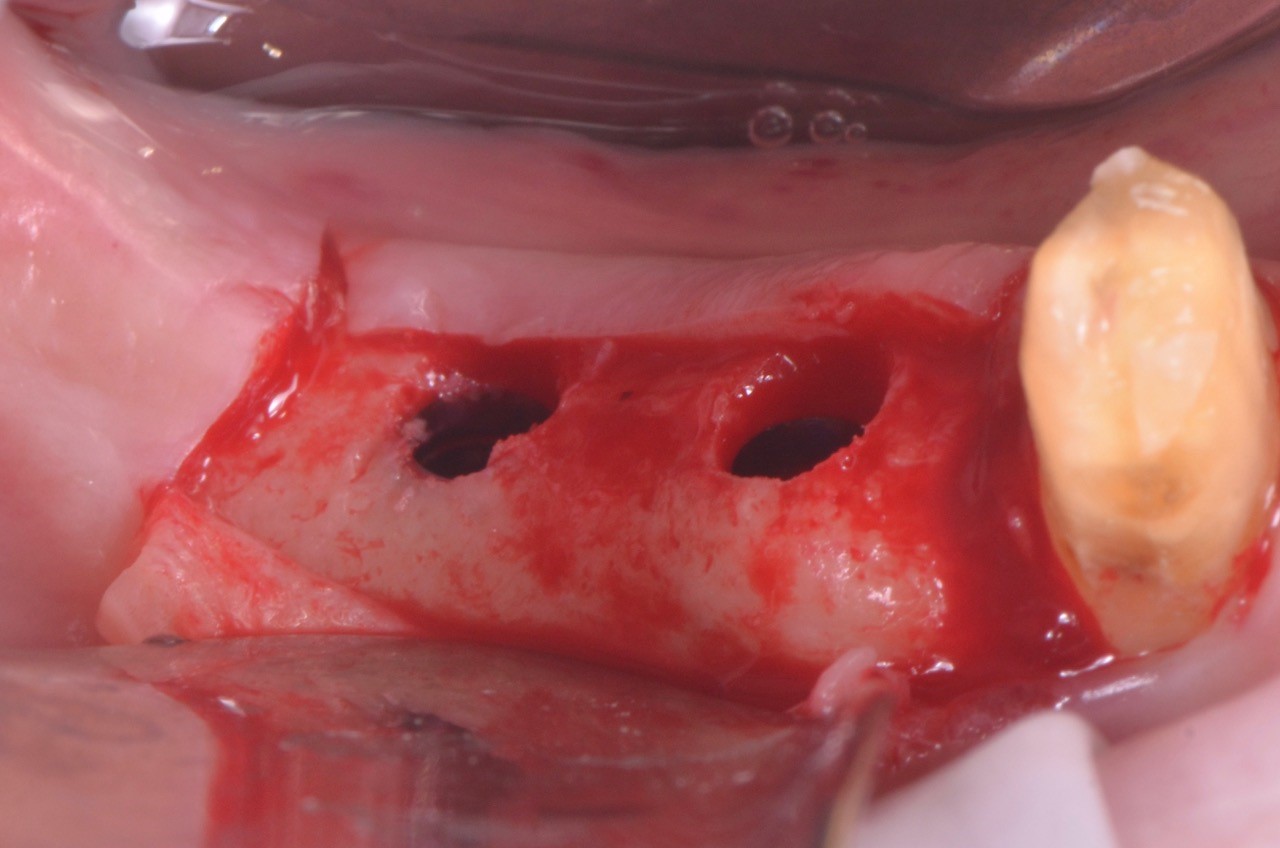

impianto-sottocrestale

Foto: impianto sottocrestale

Posizionamento sub crestale di due V3

Foto: Posizionamento subcrestale di due impianti MIS V3

Le foto di questo articolo sono state gentilmente concesse dal Dott. Federico Rivara.